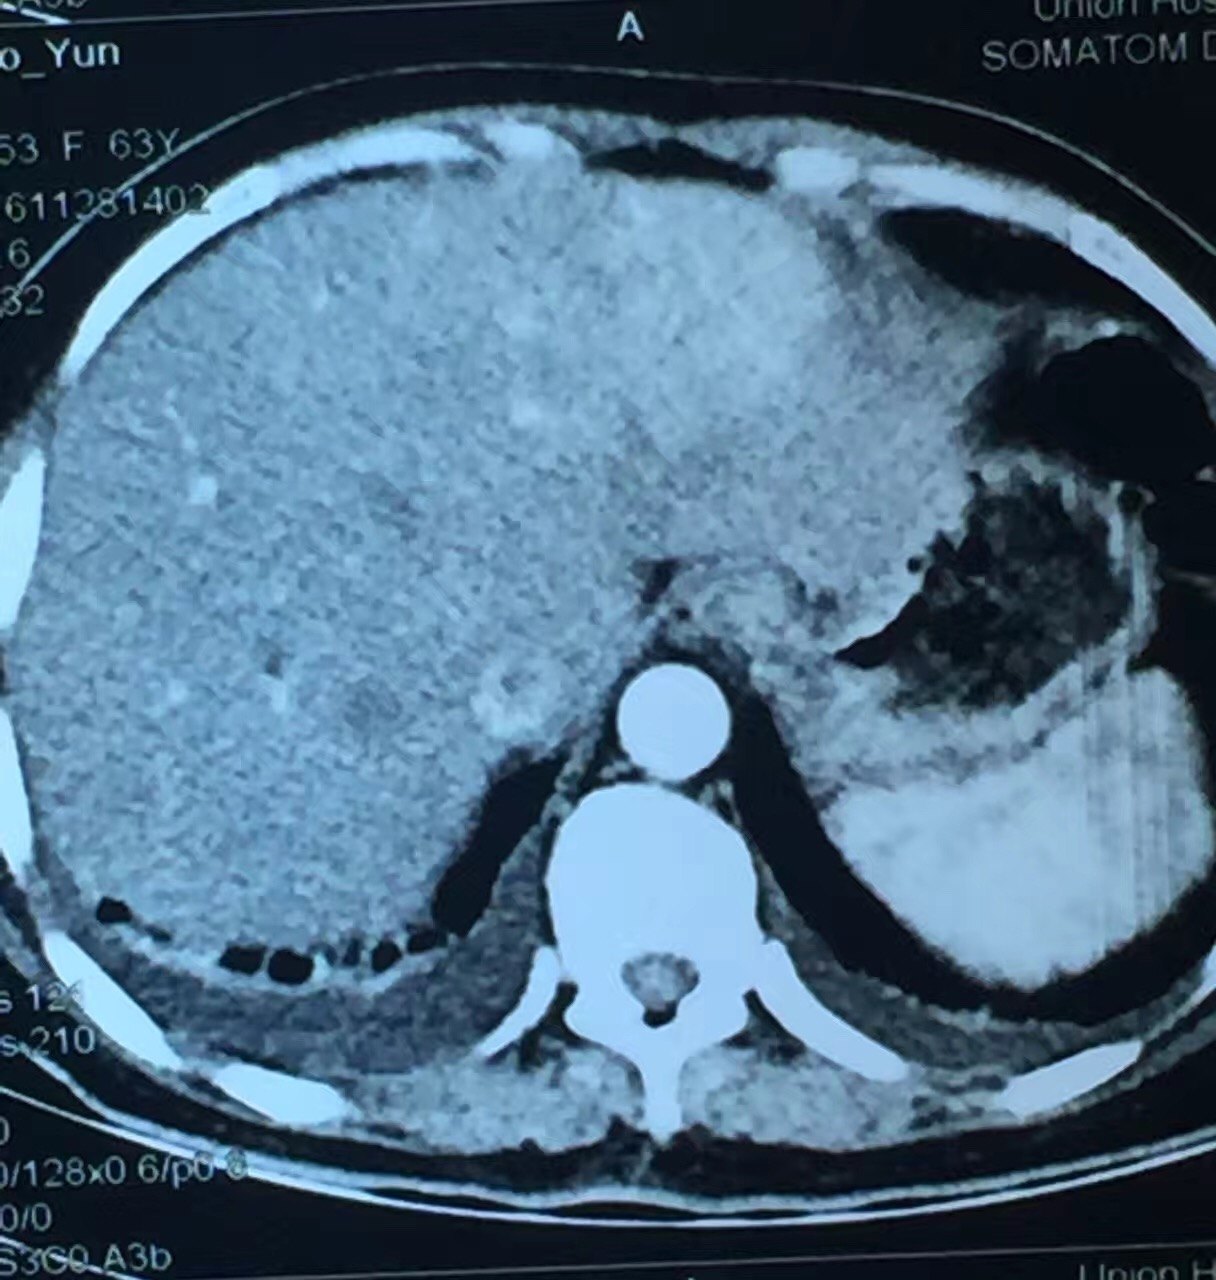

弥漫性脂肪肝伴正常肝岛一例ct增强病例

增强扫描,肝岛表现与脂肪浸润区同步均匀强化.